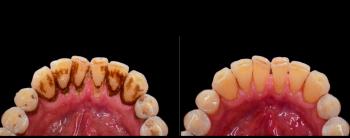

Severe Tartar Removal to Full Mouth Restoration - Case Study Philippines

A patient presented with extreme tartar buildup, gum inflammation, and discoloration. The teeth showed signs of early to advanced periodontal disease, with visible plaque deposits covering large portions of the enamel.

Treatment Performed:

Ultrasonic scaling and root planing

Deep cleaning below gumline

Polishing and antibacterial therapy

Result:

Significant improvement in gum health

Removal of hardened calculus

Brighter, cleaner teeth

Price Comparison:

USA: $800 – $2,000

Philippines: $100 – $300